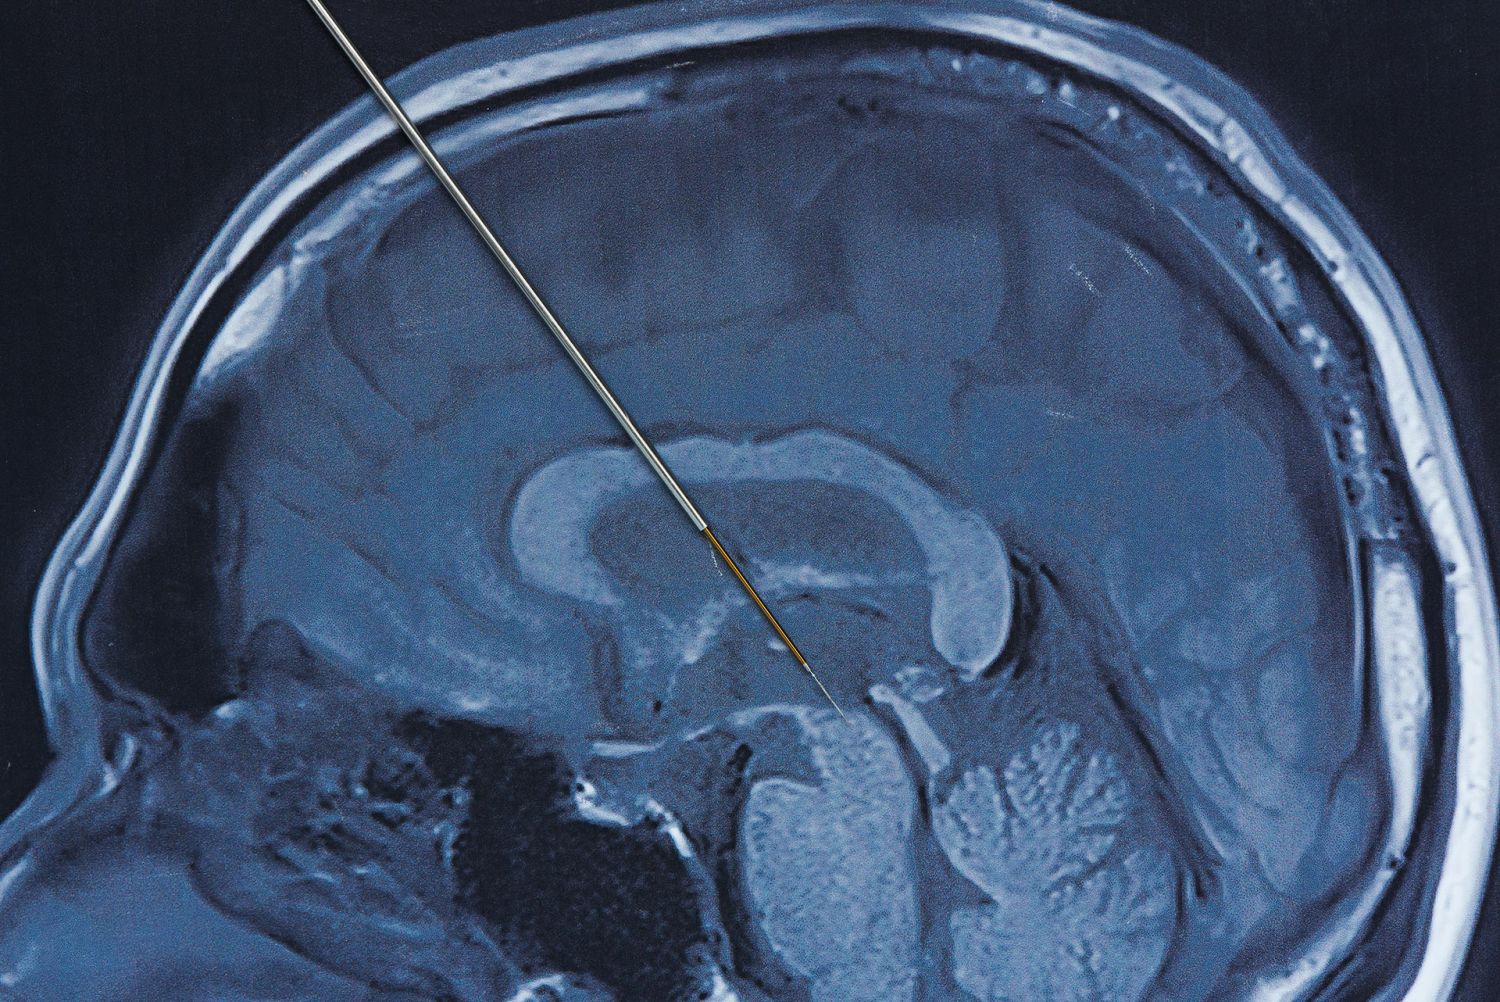

En nota de prensa, la universidad ha informdo de que los canales GirK son proteínas de la membrana neuronal y uno de los mecanismos inhibitorios que posee el sistema nervioso para controlar el exceso de excitación. Está confirmado que existen múltiples evidencias que asocian los canales GirK y las enfermedades neurológicas y psiquiátricas, como trastornos del estado de ánimo, trastorno por déficit de atención con hiperactividad (TDAH), esquizofrenia, epilepsia, síndrome de Down, Alzheimer, Parkinson, alcoholismo o drogadicción.

Un ejemplo de esos desajustes puede encontrarse en los excesos de actividad neuronal, lo que desequilibra los sistemas de neurotransmisión favoreciendo la hiperexcitación, la cual puede producirse por déficits en los sistemas de control inhibitorio. Dado que, según explican los autores del estudio, en los últimos años han adquirido gran relevancia los canales GirK como mecanismos inhibitorios del sistema nervioso para controlar el exceso de excitación, de ahí la relevancia de este estudio que pretende integrar todo el conocimiento sobre su funcionamiento.